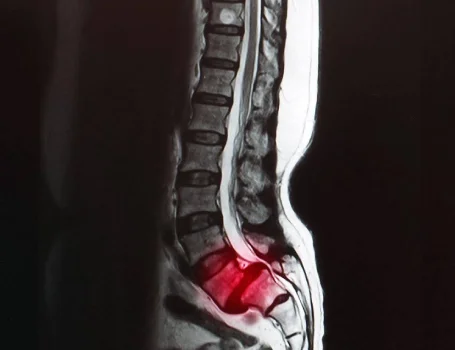

Hernia de Disco: Qué es y Cómo Afecta Tu Salud

## ¿Qué es una hernia de disco?La columna vertebral está formada por vértebras apiladas, separ...

Enfermedad del Disco Intervertebral: Causas, Síntomas y Soluciones

La enfermedad del disco intervertebral es una condición frecuente que afecta la columna vertebral, ...